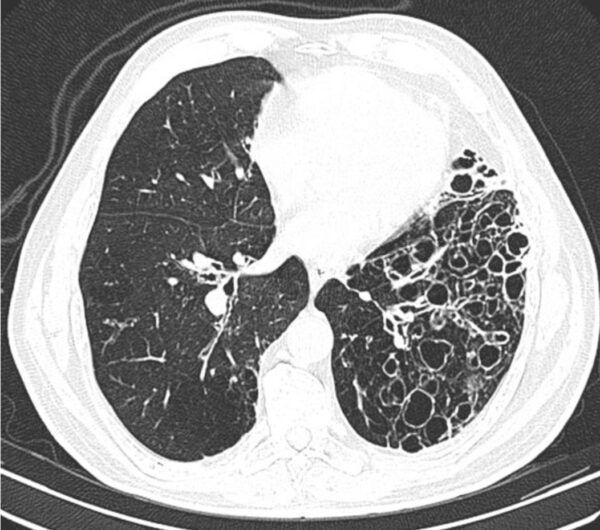

https://radiopaedia.org/cases/cystic-bronchiectasis-3

Modality

CT

Region

CHEST